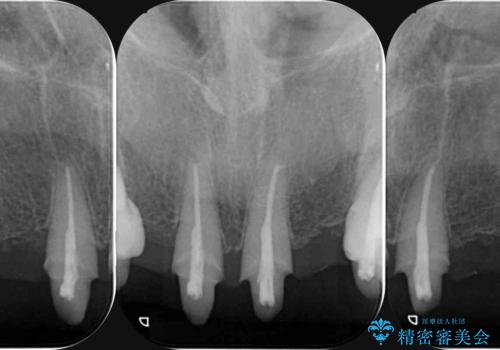

- 20年前に入れたブリッジの見た目の改善を求めて来院されました。

丁寧に現在装着されているブリッジを除去後、精度の高いジルコニアブリッジで審美性の改善を計画します。

前歯に限らず拡大鏡を用いた精密な形成・シリコンを用いた精度の高い印象を徹底することで治療全体の質を高め、審美性だけでなく長期的な予後を期待することができます。